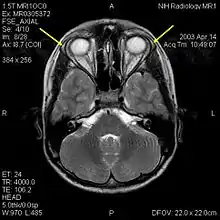

| MRI of the brain of 12-year-old boy with triple-A syndrome showing hypoplastic lacrimal glands (yellow arrows) | |